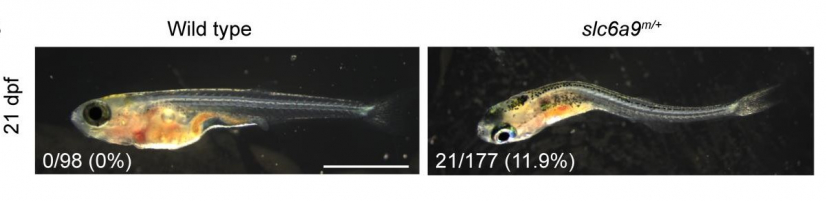

團隊的研究揭示,SLC6A9變異基因會降低甘氨酸攝取,令甘氨酸濃度提高,產生異常的神經傳遞。為了進一步驗證他們的發現,團隊利用斑馬魚模型,透過基因編輯技術破壞斑馬魚的SLC6A9基因,模擬人類AIS患者的基因變化。研究結果顯示,突變斑馬魚表現出脊柱彎曲和神經活動不協調,與AIS患者的症狀相似。

為探索AIS的潛在預防療法,研究團隊在突變斑馬魚上測試了苯甲酸鈉,這是一種臨床上用於治療甘胺酸腦患者的甘氨酸受體拮抗劑。結果顯示,苯甲酸鈉可以中度減輕斑馬魚的彎曲程度,有望為甘氨酸水平較高的AIS患者提供預防性治療。